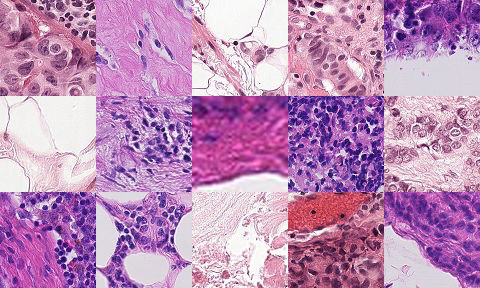

Medical Image Classification

Histopathologic Cancer Detection

Skin Cancer MNIST: HAM10000